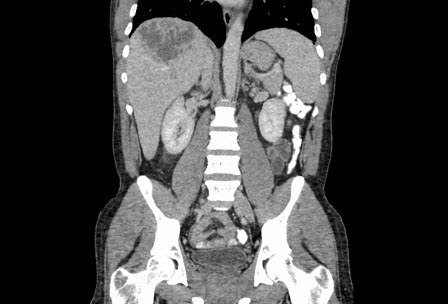

Abscesso hepático: tomografia computadorizada (TC) (vista coronal) mostrando abscesso hepático em um homem de 46 anos de idade que apresentava febre, fadiga e tosse

Do acervo de imagens radiológicas do Massachusetts General Hospital